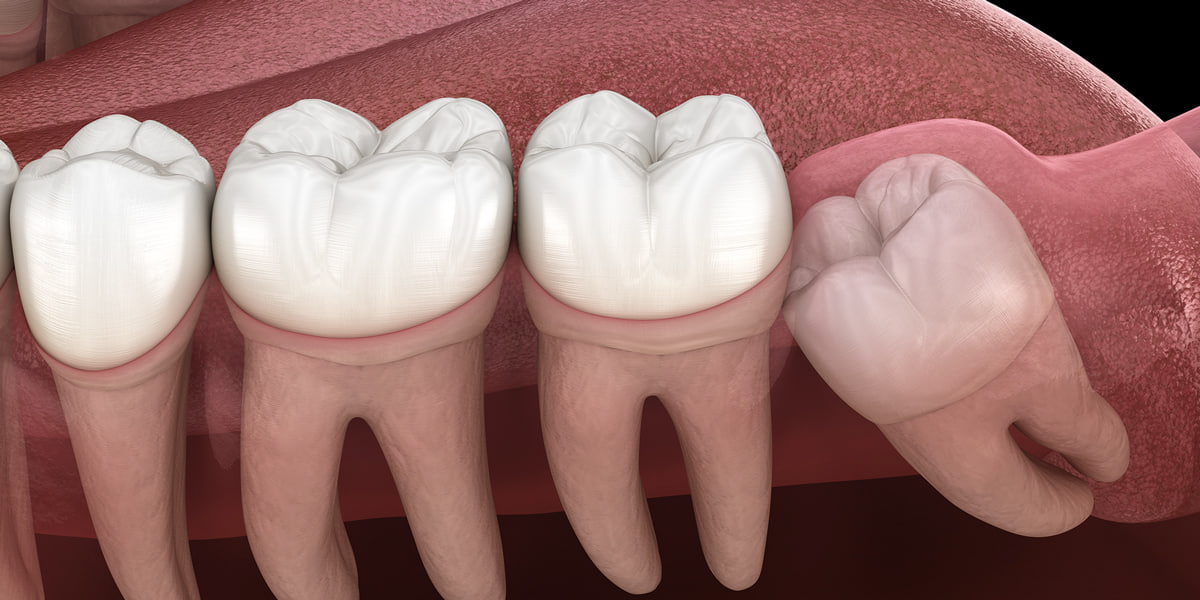

Ретинований зуб – це зуб, який сформувався в щелепі, але не зміг прорізатися. Тобто, на поверхні знаходиться лише його частина, а більшість зубної тканини залишається в кістці щелепи або під яснами. Найпоширеніша ретенція – зубів мудрості.

Операційне втручання можуть обтяжити такі фактори, як положення кореня, його розміри, викривлення або близькість до життєво важливих структур, зокрема нервів чи гайморової пазухи.